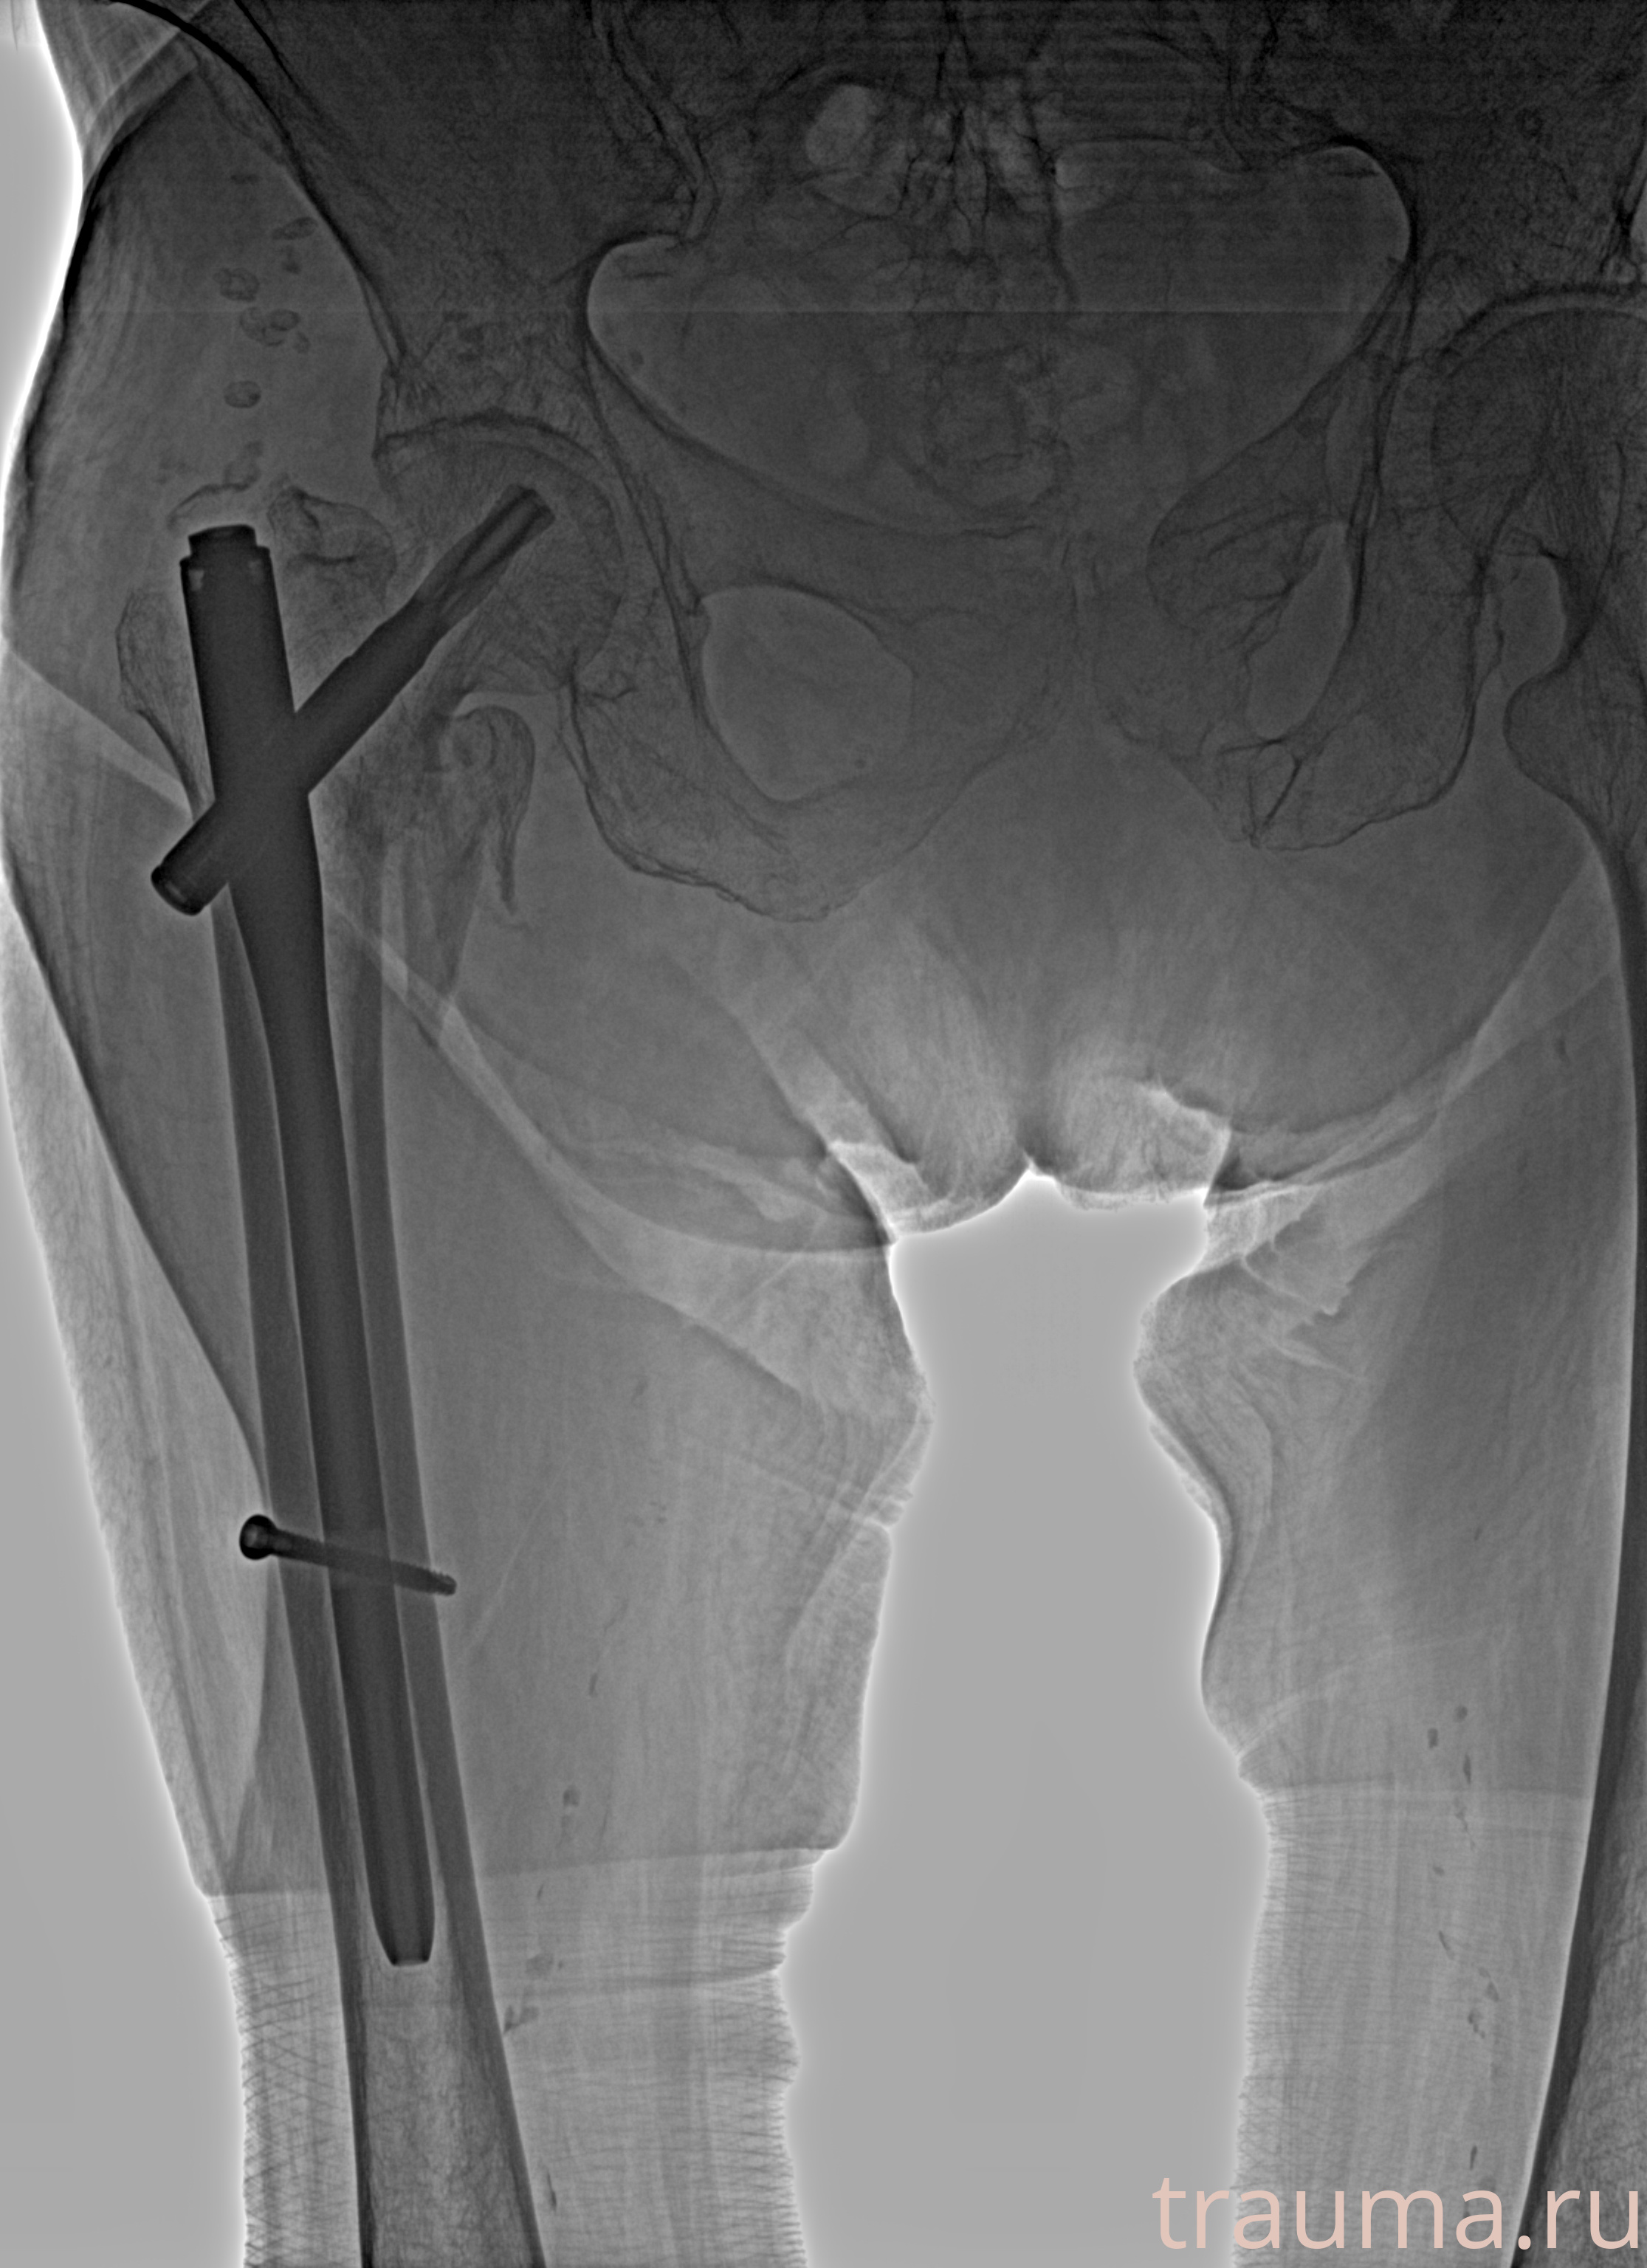

Рентген на дому: по вашему адресу приезжает врач-рентгенолог, травматолог-ортопед с мобильным рентгеновским аппаратом, проводит диагностику травмы или заболевания, делает необходимые рентгенограммы, дает рекомендации по дальнейшему лечению. Получить качественные снимки в домашних условиях возможно благодаря уникальной методике, разработанной МосРентген Центром для института  Склифосовского

при переломе шейки бедра и пневмонии от компании МосРентген Центр - партнера Института имени Склифосовского